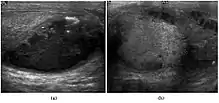

The incidence of infertility is decreased if surgical orchiopexy is carried out before the 1–3 years but the risk of malignancy does not change. Because of the superficial location of the inguinal canal in children, sonography of undescended testes should be performed with a high frequency transducer. At ultrasound, the undescended testis usually appears small, less echogenic than the contralateral normal testis and usually located in the inguinal region [Fig. 29]. With color Doppler, the vascularity of the undescended testis is poor.

![Fig. 29. Undescended testis. (a) Normal testis in the scrotum. (b) Atrophic and decreased echogenicity of the contralateral testis of the same patient seen in the inguinal region.[citation needed]](../I/Scrotal_ultrasonography_of_undescended_testis.jpg.webp) Fig. 29. Undescended testis. (a) Normal testis in the scrotum. (b) Atrophic and decreased echogenicity of the contralateral testis of the same patient seen in the inguinal region.

Fig. 29. Undescended testis. (a) Normal testis in the scrotum. (b) Atrophic and decreased echogenicity of the contralateral testis of the same patient seen in the inguinal region.